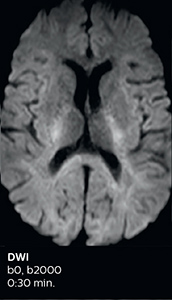

Using MultiBand SENSE allowed the staff to improve their diffusion quality. “Our diffusion sequence was already fast before, about 40 seconds. Now with Elition, it still lasts 40 seconds, but we improved the spatial resolution by 0.2 mm and use high b-values to be more sensitive to visualize changes related to acute stroke,” says Dr. Savatovsky. “We now also developed a high resolution DTI sequence (1.3 x 1.3 x 2 mm) that can be reformatted and takes 2 to 5 minutes depending on the coverage. We use it every time we have a doubt, or when we expect the diffusion to be abnormal but don’t see that on the fast sequence. We occasionally spot small ischemic infarctions that would not have been visible with the regular diffusion sequence.”

This is an example of acute ischemic stroke with distal occlusion of the right posterior cerebral artery. Note the improved visibility of the ischemic territory on the diffusion weighted image with high b-value. The 3D FLAIR shows a distal PCA occlusion. The fast SWIp depicts the thrombus on the isolated second echo image. The total scan time (including SmartBrain, preparations and a fast 3D T1w TSE Gd) is 8:00 minutes.

In this patient with acute right motor deficit and aphasia, the b2000 diffusion weighted image is normal. The SWIp image demonstrates more prominent veins in the right hemisphere, which could reflect increased deoxyhemoglobin contents. Fast ASL shows low CBF regions in the left frontal lobe. A follow-up ASL after one hour demonstrates high CBF values in the same area. The final diagnosis was migraine with aura.